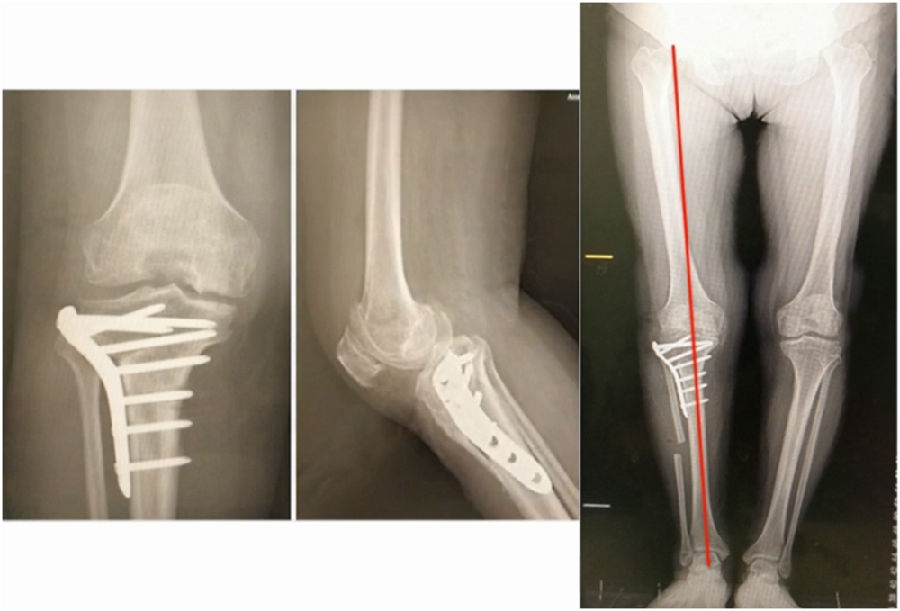

典型病例,男性,57岁,农民,左膝疼痛3年。

术前

术前影像资料

术前规划:

①关节内截骨,内外侧平台平行。

关节内截骨

②再次确定下肢力线。

确定力线

③关节外截骨。

关节外截骨

术中先打克氏针确定截骨方向,先做关节内截骨,截完后测量下肢力线,发现并没达到术前设计的Fujisawa点。

术中影像资料

随后用骨刀继续向前敲,做HTO内侧开放楔,截骨完成后内侧固定,并测量下肢力线,此时达到术前设计的要求。

该患者撑开较大,取了髂骨进行植骨。

术后检查证实达到了术前预期的手术效果,关节线达到了平行,半脱位得到矫正,同时关节线和地面水平。病人行走达到了理想的效果。

术后X线

患者术后4个月截骨愈合,膝关节稳定维持得非常好。

术后4个月